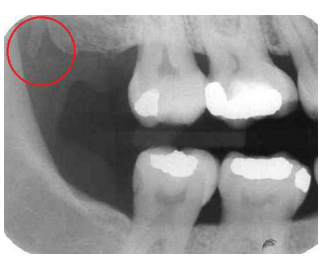

A estrutura que aparece atrás do túber da maxila, destacada na imagem abaixo, denomina-se: